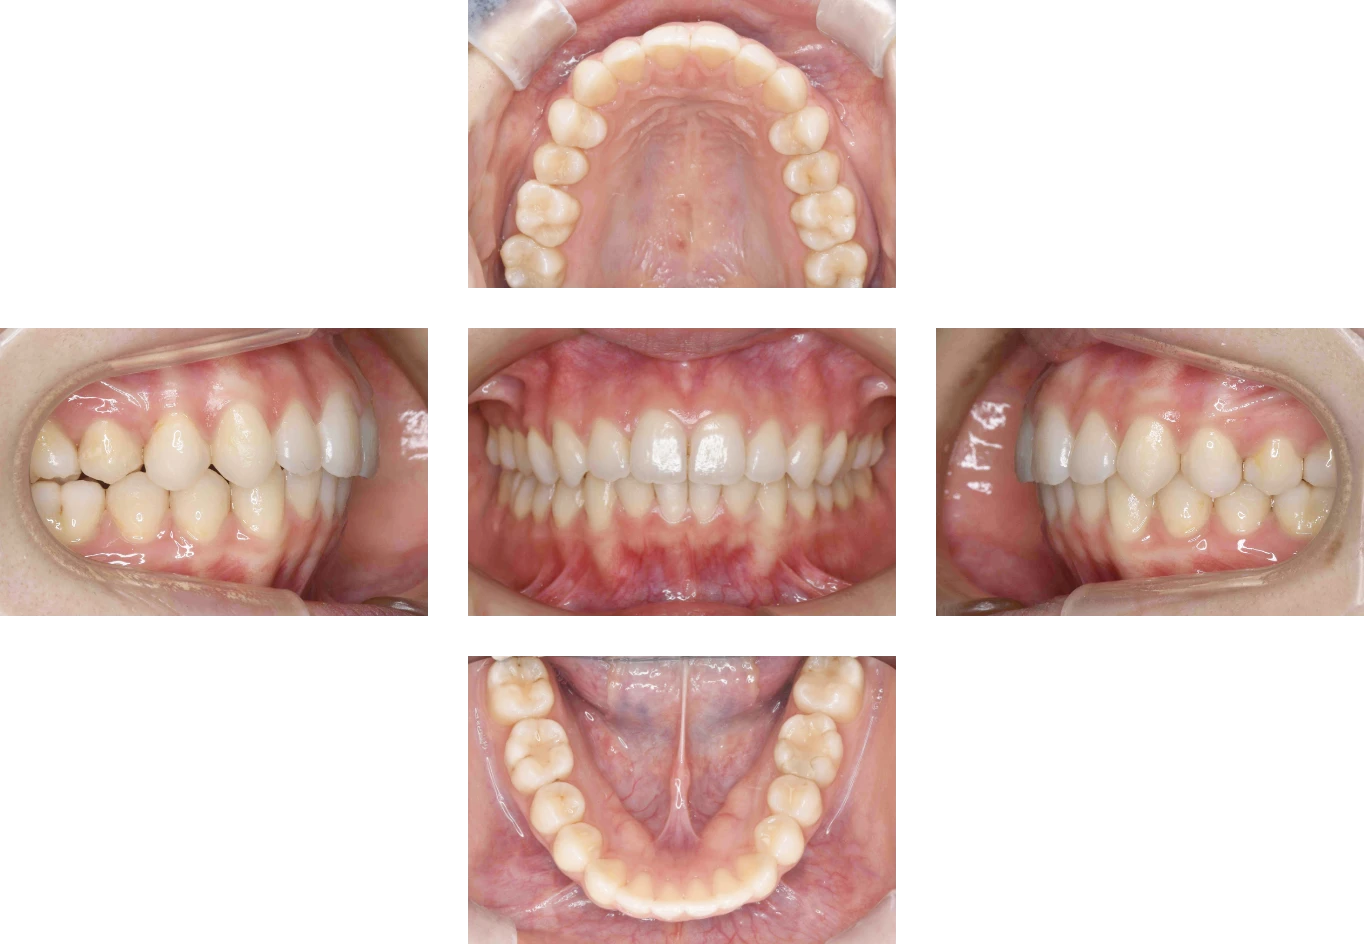

Case4

| 主訴 | 前歯が出ている |

| 診断名 | 上顎前突 |

| 年齢 | 19歳 |

| 治療に 用いた装置 |

リンガルブラケット矯正装置(エッグブラケット) |

| 抜歯部位 | 非抜歯 |

| 治療期間 | 2年7ヶ月 |

| 治療費用 | 1,385,100円 |